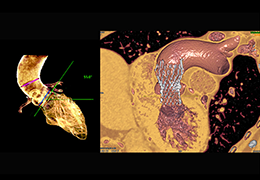

View X-Ray CT & MRI Scans Fast and Easily

Designed for surgeons, Pro Surgical 3D makes it easy to view patient scans quickly. Pro Surgical 3D facilitates the optimal 3D treatment and assessment workflows based on X-ray CT and MRI scans – and best of all, it’s FREE!

Traditional multi-planar slicing

High-quality and fast 3D reconstruction and 3D rendering

Performs 3D reconstruction and volume rendering.

Multi-planar slicing.

Side-by-side comparative assessment for pre- and post-operative scans.